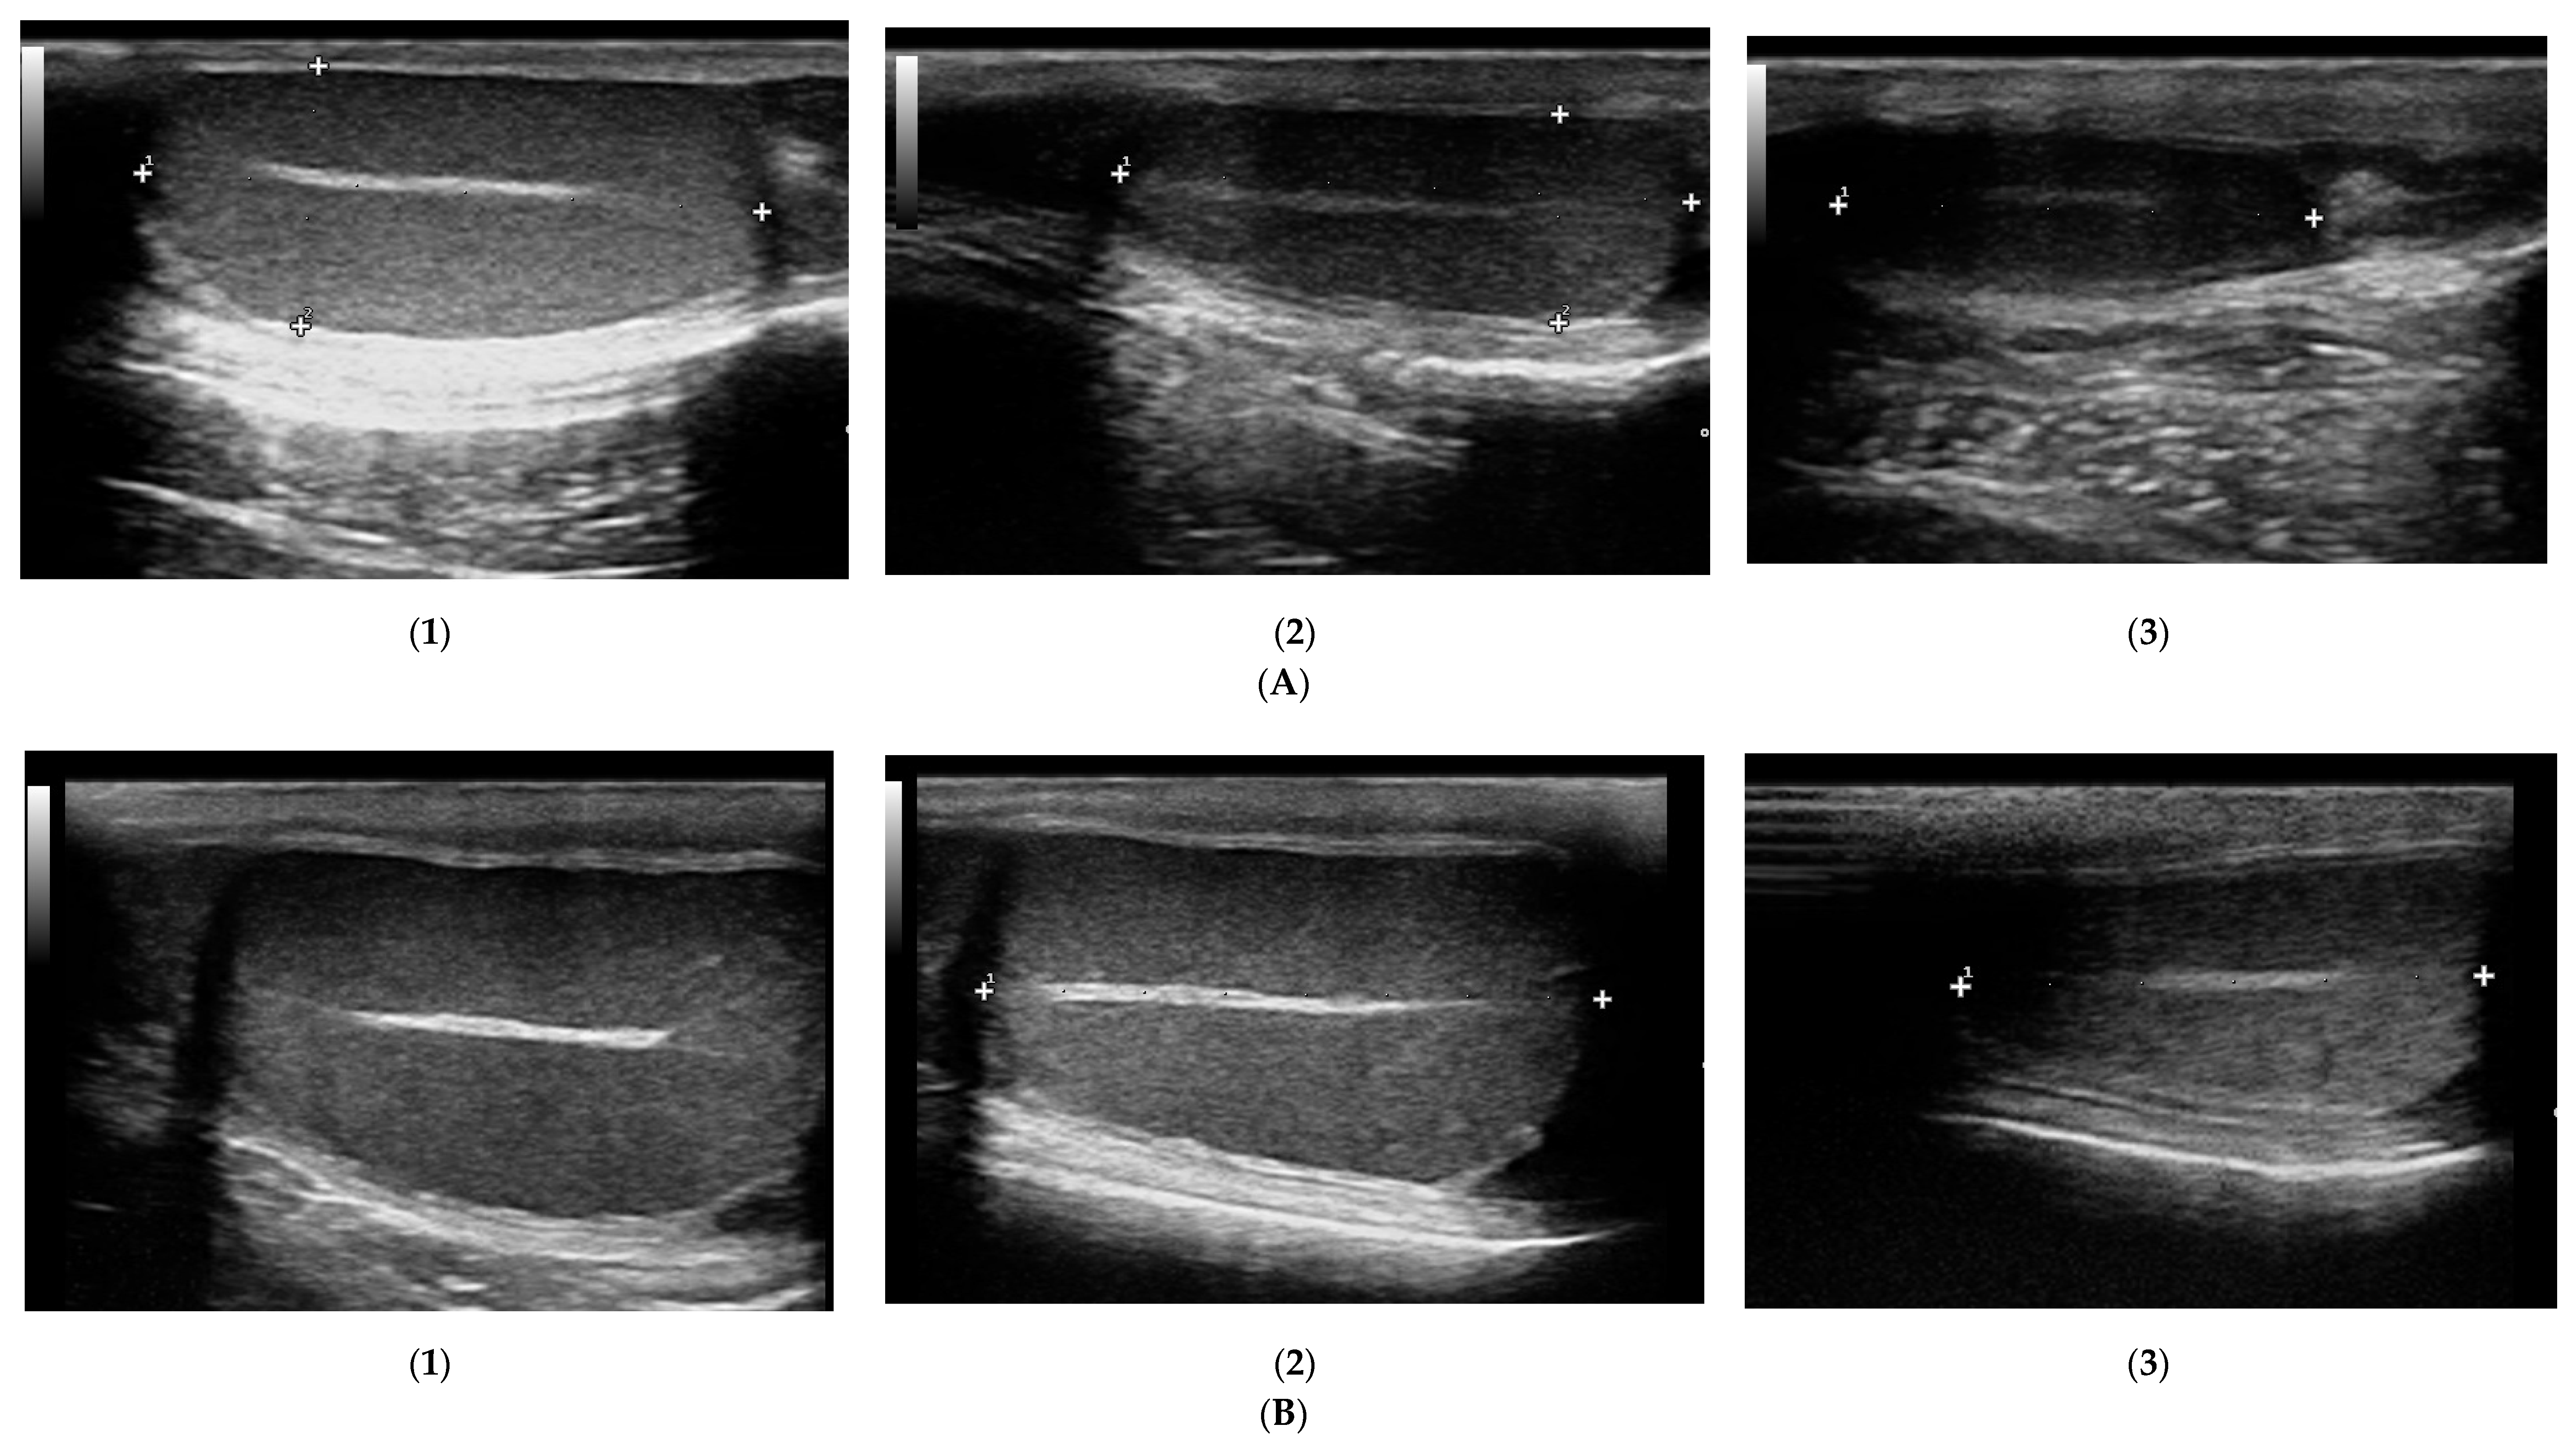

3.3. Testicles B-Mode Appearance

3.4. Doppler Ultrasonography of the Testicular Artery